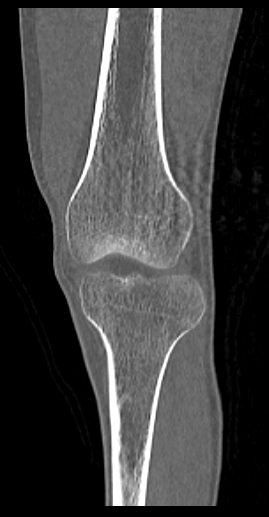

Одним из наиболее информативных методов исследования коленных суставов является мультиспиральная компьютерная томография. КТ относится к лучевым методам исследования и основана на применении ионизирующего излучения с последующей цифровой обработкой данных, полученных при КТ-сканировании.

В наших медицинских центрах обследование коленного сустава проводится на современных мультиспиральных компьютерных томографах последнего поколения TOSHIBA AQUILION. При помощи рентгеновских лучей аппараты послойно сканируют в разных плоскостях исследуемую область с толщиной среза от 0,5 мм. В результате получаются детальные снимки и цифровые трехмерные изображения коленного сустава в мельчайших подробностях. Помимо точности и достоверности диагностики современные компьютерные томографы обеспечивают для пациента минимальную дозу рентгеновского облучения.

Мультиспиральная компьютерная томография дает возможность оценить структуру костной ткани, выявить переломы, воспалительные изменения, участки деструкции костей и диагностировать опухолевые образования. Мультиспиральная КТ часто применяется в ортопедии и травматологии. За счет быстроты, доступности и неинвазивности (то есть обследование выполняется без вмешательства в организм) метод незаменим при травмах сустава, а также при планировании оперативных вмешательств, например, в случае эндопротезирования сустава. В послеоперационном периоде КТ помогает оценить эффективность проведенной операции, вовремя выявить осложнения и отследить процесс восстановления.

Что показывает КТ коленного сустава

- переломы костей;

- артроз;

- артрит;

- скопление жидкости в суставе;

- кисту Бейкера;

- костные наросты на поверхности сустава;

- новообразования

- полные или неполные вывихи — по смещению образующих сустав элементов относительно друг друга;

- деформирующий остеоартроз, ревматический полиартрит

- злокачественную или доброкачественную опухоль

- гемартроз

- абсцесс.